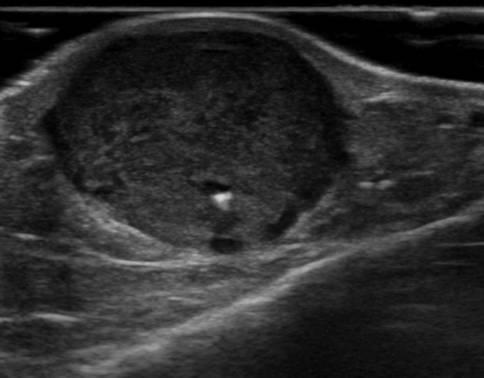

U máu

U máu - Ảnh 2

» Thông tin: Nam giới – 66 tuổi.

» Lâm sàng: Sưng cẳng chân.